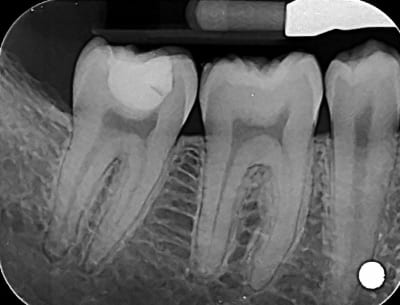

du coup j'ai revu le patient

j'ai démonté le soin, j'ai vu le fond de cavité que j'ai deposé mais pas de carie dessous visible

j'ai remis de la résine sans fond de cavité,

J'ai prévenu le patient des risques de sensibilité post op qui pouvaient venir à cause de fait que j'ai déposé le fond de cavité. Et que s'il y avait des sensibilités, il faudrait dévitaliser la dent.

Tu vois , ils se foutaient de notre tronche quand on disait qu’ il y avait un fond de cavité sans carie :) Ils m’ont même mis le doute les deux:)

Perso j aurais jamais pensé voir un truc aussi propre... j' avais vraiment tort. Désolé...

Je pensais trouver une dentine noire ébène... Ramollie mais assez dure... De la carie a progression très lente.

Du coup c'était quoi le fond de cav ?? Ça sentait l eugenol ??